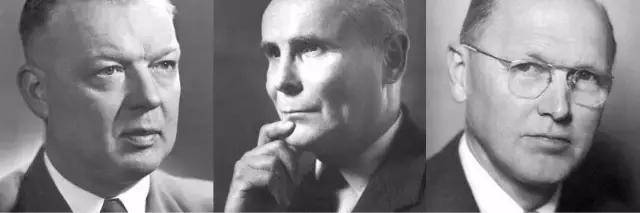

1956年諾貝爾生理學/醫學獎獲得者(福斯曼、考南德和查理茲)

直到1956年的10月,福斯曼與另外兩位美國學者共同獲得諾貝爾生理學/醫學獎的消息傳遍了全球,他才終於為世人所知。

這位被學術界遺忘了20多年的鄉村醫生,被學術界譏笑為「小丑」的「瘋子」,終於殺回了自己的主戰場。

他先後成為了德國外科學會委員、美國胸科醫師學會委員、瑞士心臟病學會委員…